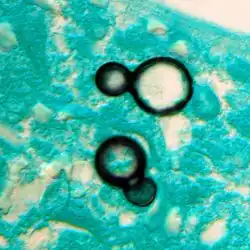

Large, broadly-based budding yeast cells characteristic of Blastomyces dermatitidis in a GMS-stained biopsy section from a human leg.

Inhaled conidia of Blastomyces are phagocytosed by neutrophils and macrophages in alveoli. Some of these escape phagocytosis and transform into the yeast phase rapidly. Having thick walls, these are resistant to phagocytosis. Once they have transitioned to the yeast phase, the Blastomyces cells express the protein BAD-1, which helps the yeast cells attach to host cells, and also impairs the activation of immune cells while inhibiting the release of tumor necrosis factor. [23] In lung tissue, the cells multiply and may also disseminate through blood and lymphatics to other organs, including the skin, bone, genitourinary tract, and brain. The incubation period for pulmonary blastomycosis is 3 to 15 weeks, although 30–50% of infections are asymptomatic.[24]

Once suspected, the diagnosis of blastomycosis can usually be confirmed by demonstration of the characteristic broad-based budding organisms in sputum or tissues by KOH prep, cytology, or histology.[27] Tissue biopsy of the skin or other organs may be required to diagnose extra-pulmonary disease. Blastomycosis is histologically associated with granulomatous nodules.